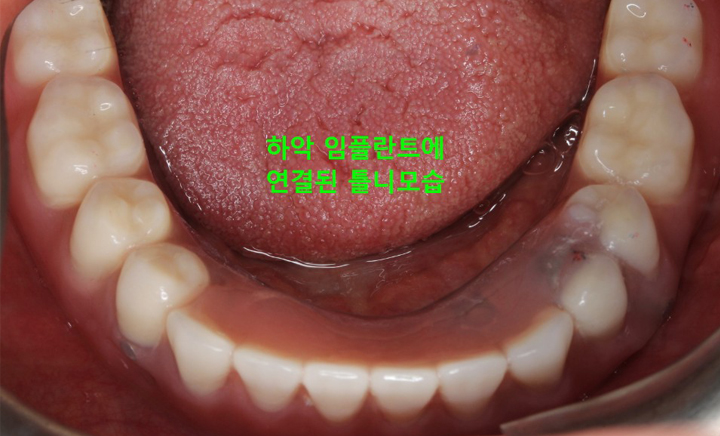

환자분 상태에 따라 임플란트를 2개에서 4개 정도만을 식립하고

그 위에 틀니를 고정시키는 치료 방법

그리고 위턱의 틀니는 입천장이 있어 그나마 고정이 잘되지만 아래턱은 그런 구조물도 없는데다 혀가 자꾸 방해하기 때문에 고정하기가 쉽지 않아 틀니가 움직이는 불편함이 생깁니다. 이러한 틀니의 단점을 보완하고 틀니의 경제성과 임플란트의 기능성을 결합해 만들어진 것이 틀니 임플란트 입니다.